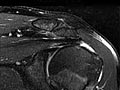

Magnetic Resonance Imaging (MRI) of the Shoulder

Magnetic Resonance Imaging (MRI) of the ShoulderSkip to the navigationTest OverviewMagnetic resonance imaging (MRI) is a test